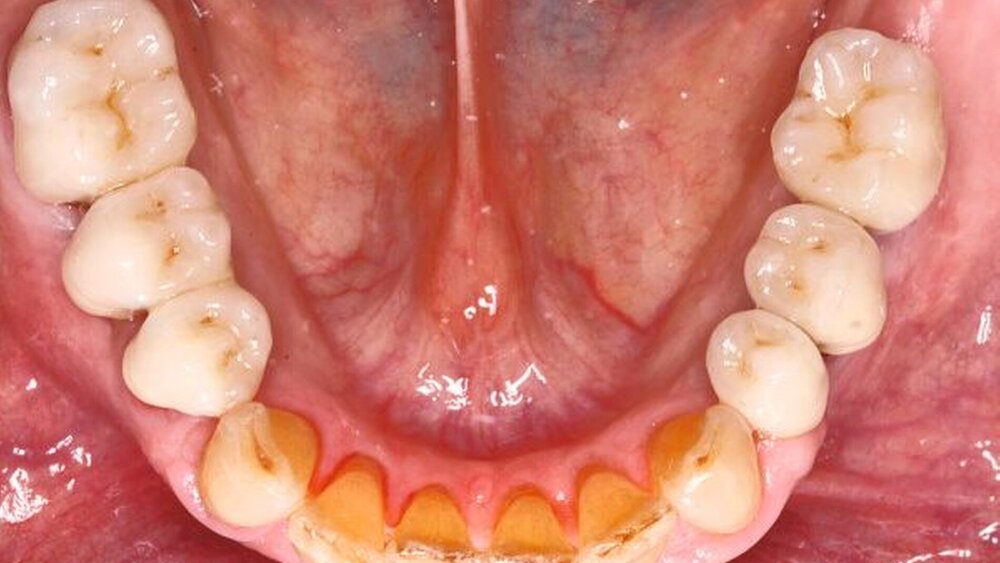

Dentale und parodontale Voraussetzungen

Als diagnostische Maßnahmen werden vor einer Überkronung eine Sensibilitätsprüfung sowie eine röntgenologische Kontrolle durchgeführt. Die Vorbehandlung vor einer Überkronung umfasst die chirurgische, konservierende und parodontale Sanierung, der Pfeilerzähne. Das Substanzangebot sollte bei allen Formen von Brücken für eine retentive Präparation ausreichend sein, da mangelnde mechanische Retention in klinischen Studien als Hauptursache für ein technisches Versagen angegeben wird [Hammerle et al., 2000].

Wenn als Brückenpfeiler endodontisch behandelte Zähne herangezogen werden, so erhöhen diese im Vergleich zu vitalen Pfeilerzähnen das Komplikationsrisiko bei Endpfeilerbrücken [De Backer et al., 2006; Salvi et al., 2007] und insbesondere bei Extensionsbrücken [De Backer et al., 2007; Decock et al., 1996]. Der Anteil von Misserfolgen aufgrund von Zahnfrakturen ist gering, häufiger kommt es zu endodontischen, parodontalen und technischen Misserfolgen [Hämmerle et al., 2000; Pjetursson et al., 2004]

Liegt eine Parodontalerkrankung vor, ist eine präprothetische parodontale Vorbehandlung Grundvoraussetzung für den Langzeiterfolg festsitzenden Zahnersatzes. Wird sie erfolgreich durchgeführt, sind auch ausgedehntere Brücken indiziert [De Boever, 1990].

Gute Mundhygiene ist für den Langzeiterfolg besonders wichtig. Sekundärkaries ist die häufigste Ursache für biologische Misserfolge, viermal so häufig wie das Versagen aus parodontalen Gründen [Tan et al., 2004].